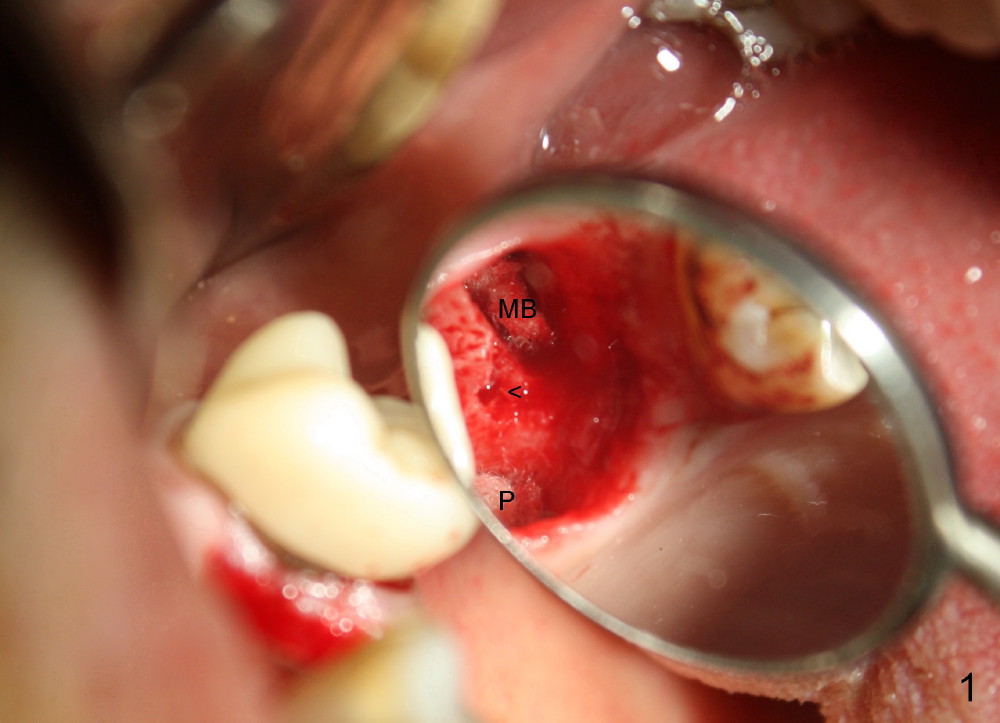

The upper left 1st molar is extracted with sectioning. The septum is large. A surgical fissure bur is used to initiate an osteotomy in the middle of the septum (Fig.1 <; P: palatal socket, MB: mesiobuccal socket), followed by tapping with resistance a 2 mm osteotome ~ 8 mm into the septum. It is tougher to drive 3 mm osteotomy. A 2.5 mm reamer is used to enlarge the osteotomy at 50 RPM at the same depth. Then it is relatively easy to tap 3 and 4 mm osteotomes at ~ 8 mm into the septum. A 4.5x17 mm tap is inserted 8 mm deep with binding to the septum. PA is taken (Fig.2). It appears that the sinus floor (black >) has been penetrated, but the osteotomy has not reached the apex (white >) of the palatal (P) socket. Then the tap is advanced ~ another 3 mm. When the tap is removed, the osteotomy (Fig.3 O) is slightly toward the buccal aspect of the extraction socket, but it has intact wall, including the mesiobuccal (>). The apex of the ostoetomy has no bone, but there is no air leakage. The next tap, 5x17 mm, is inserted shallower (~ 8 mm in the septum; to reduce potential trauma) with stability. However, 6x17 mm tap at the same depth does not obtain stability, since the osteotomy deviates severely mesiobuccally (Fig.4 arrow) with breakdown of the mesiobuccal wall. So the osteotomy has to be deeper in order to achieve stability of 6x17 mm tap (by engaging into more apical bone). A 7x17 mm tap is then intended to be inserted to close the socket as much as possible, but as it is being inserted, the osteotomy is more severely deviated and tilted mesiobuccally with the original mesiobuccal wall further being broken down (not shown). It appears to compromise stability. Mixture of autogenous bone from reamer, allograft and synthetic bone is placed in the mesiobuccal and palatal sockets before placement of the 6x17 mm implant (Fig.5 I). Unfortunately some of graft blocks the apical osteotomy. To clear the blockage, some of previous osteotome and taps are re-inserted. The result is in fact beneficial, as bone graft (G) is pushed upward. Prior to implant placement, nose blowing test does not produce air leakage. More allograft is placed in the coronal portion of the sockets (Fig.6 G); an abutment with precut slots is placed (A) with intention of better holding perio dressing in place after placement of a collagen dressing (Fig.7 M). A temporary crown may be placed when the perio dressing is dislodged. The provisional is to keep the membrane and bone graft in place. The patient returns for follow up 1 week postop. He is symptom free. The abscess appears to be resolving (Fig.8 >); the perio dressing remains in place.